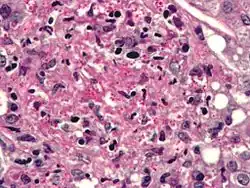

Cryptococcus

Cryptococcus neoformans can cause a severe form of meningitis and meningo-encephalitis in patients with HIV infection and AIDS. The majority of Cryptococcus species live in the soil and do not cause disease in humans. Cryptococcus neoformans is the major human and animal pathogen. Papiliotrema laurentii and Naganishia albida, both formerly referred to Cryptococcus, have been known to occasionally cause moderate-to-severe disease in human patients with compromised immunity. Cryptococcus gattii is endemic to tropical parts of the continent of Africa and Australia and can cause disease in non-immunocompromised people.[1]

Infecting C. neoformans cells are usually phagocytosed by alveolar macrophages in the lung.[11] The invading C. neoformans cells may be killed by the release of oxidative and nitrosative molecules by these macrophages.[12] However some C. neoformans cells may survive within the macrophages.[11] The ability of the pathogen to survive within the macrophages probably determines latency of the disease, dissemination and resistance to antifungal agents. In order to survive in the hostile intracellular environment of the macrophage, one of the responses of C. neoformans is to upregulate genes employed in responses to oxidative stress.[11]

The haploid nuclei of C. neoformans can undergo nuclear fusion (karyogamy) to become diploid. These diploid nuclei may then undergo meiosis, including recombination, resulting in the formation of haploid basidiospores that are able to disperse.[13] Meiosis may facilitate repair of C. neoformans DNA in response to macrophage challenge.[13][14]